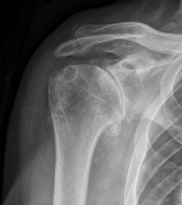

Η διάγνωση τίθεται από το ιστορικό του ασθενούς, την κλινική εξέταση και τις απλές ακτινογραφίες. Στις απλές ακτινογραφίες ο ορθοπαιδικός αξιολογεί την ύπαρξη οστεόφυτων και τη στένωση του μεσάρθριου διαστήματος.

Αρθρίτιδα ώμου